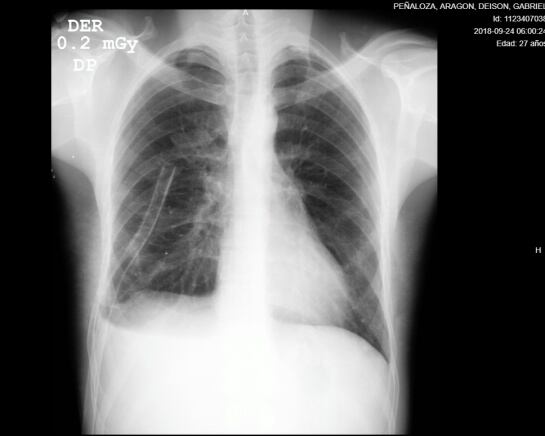

Luego de completar su recuperación en el servicio de hospitalización con ejercicios de incentivo respiratorio, Deyson fue dado de alta y se estima que, siguiendo una serie de recomendaciones y controles periódicos, muy pronto pueda retomar sus actividades diarias.